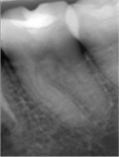

Paciente de sexo masculino de 23 años, con piezas 27 y 28 con caries profunda, ecosistema cerrado y cámaras amplias en análisis clínico radiográfico (figs. 4a,b). Se plantea tratamiento conservador en 27 y extracción en 28 ya que no ocluye con antagonista. En 27 se abre esmalte socavado, se elimina con cucharita la dentina necrótica reblandecida superficial, constatando ligera sensibilidad sin comunicación. En el análisis dentinario se observa dentina de color amarillo, blanda y húmeda, o sea con las características de una caries muy activa (Fig 4c).